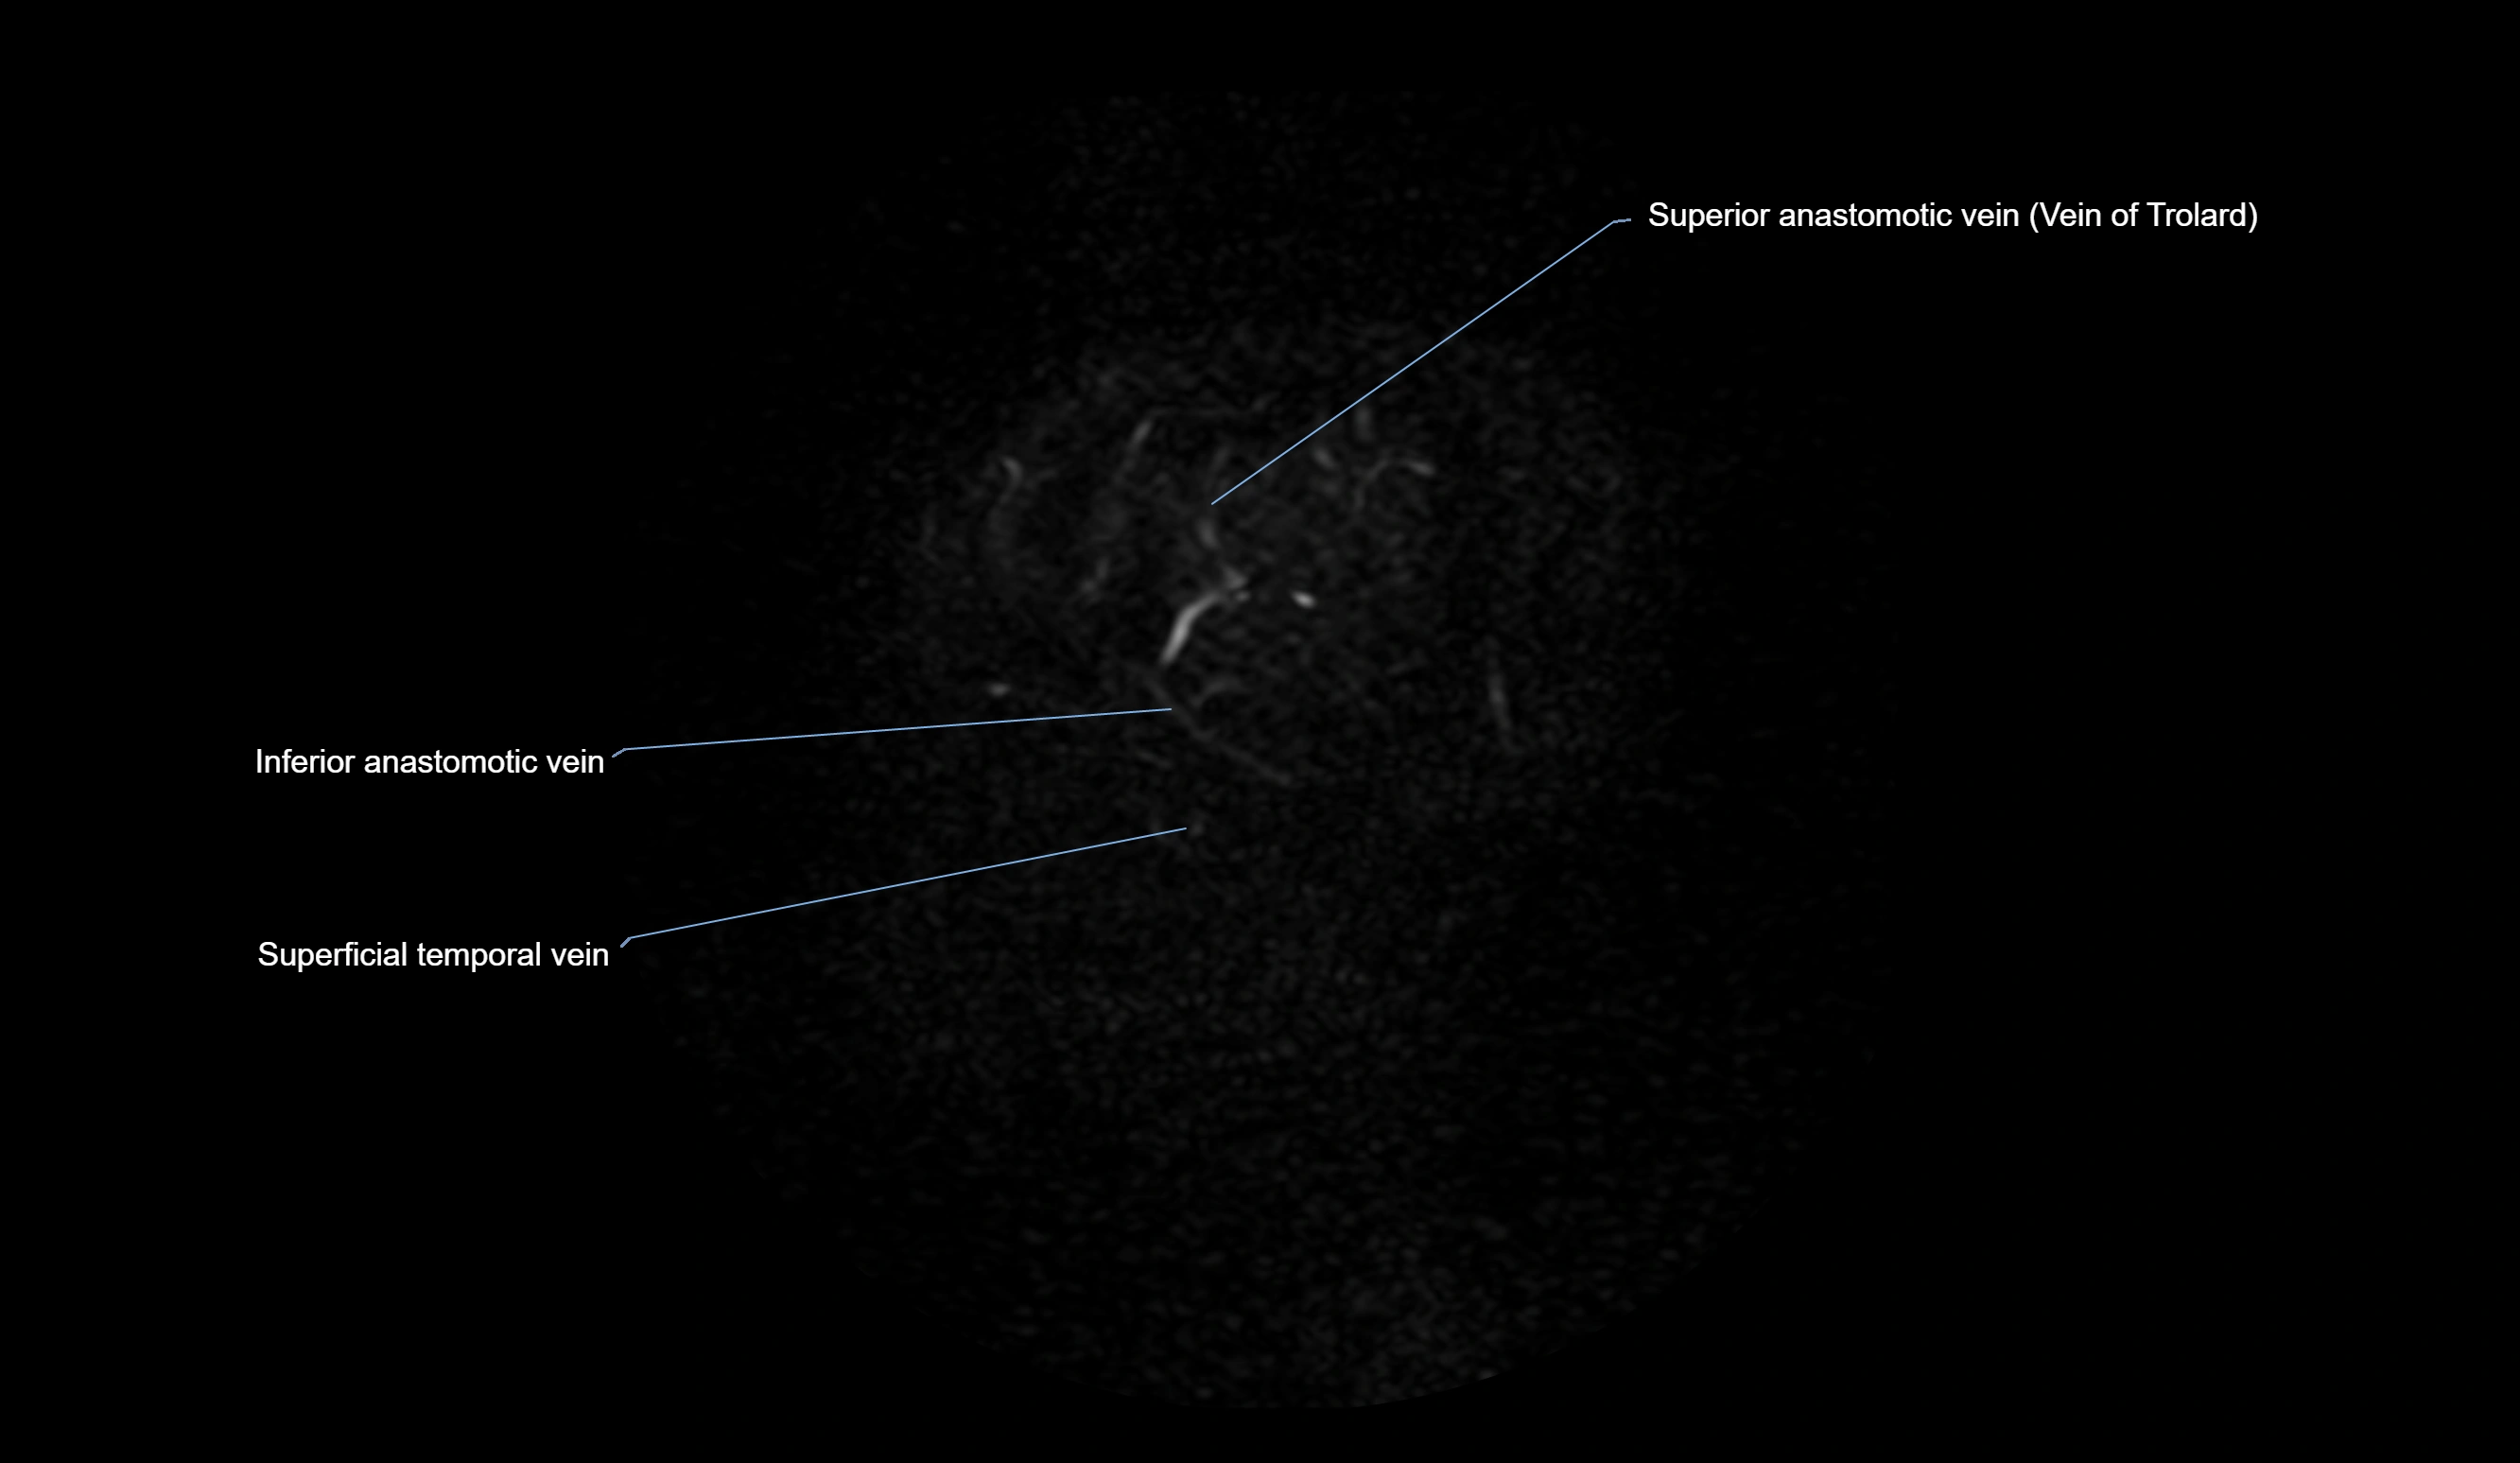

MRI Appearance

MR Venography (MRV):

• Time-of-flight (TOF) or contrast-enhanced MRV shows the angular vein as a bright enhancing venous channel

• Clearly demonstrates its continuity with the facial vein and superior ophthalmic vein

• MRV is highly useful in evaluating thrombosis, venous obstruction, or collateral venous drainage

MRI images

image